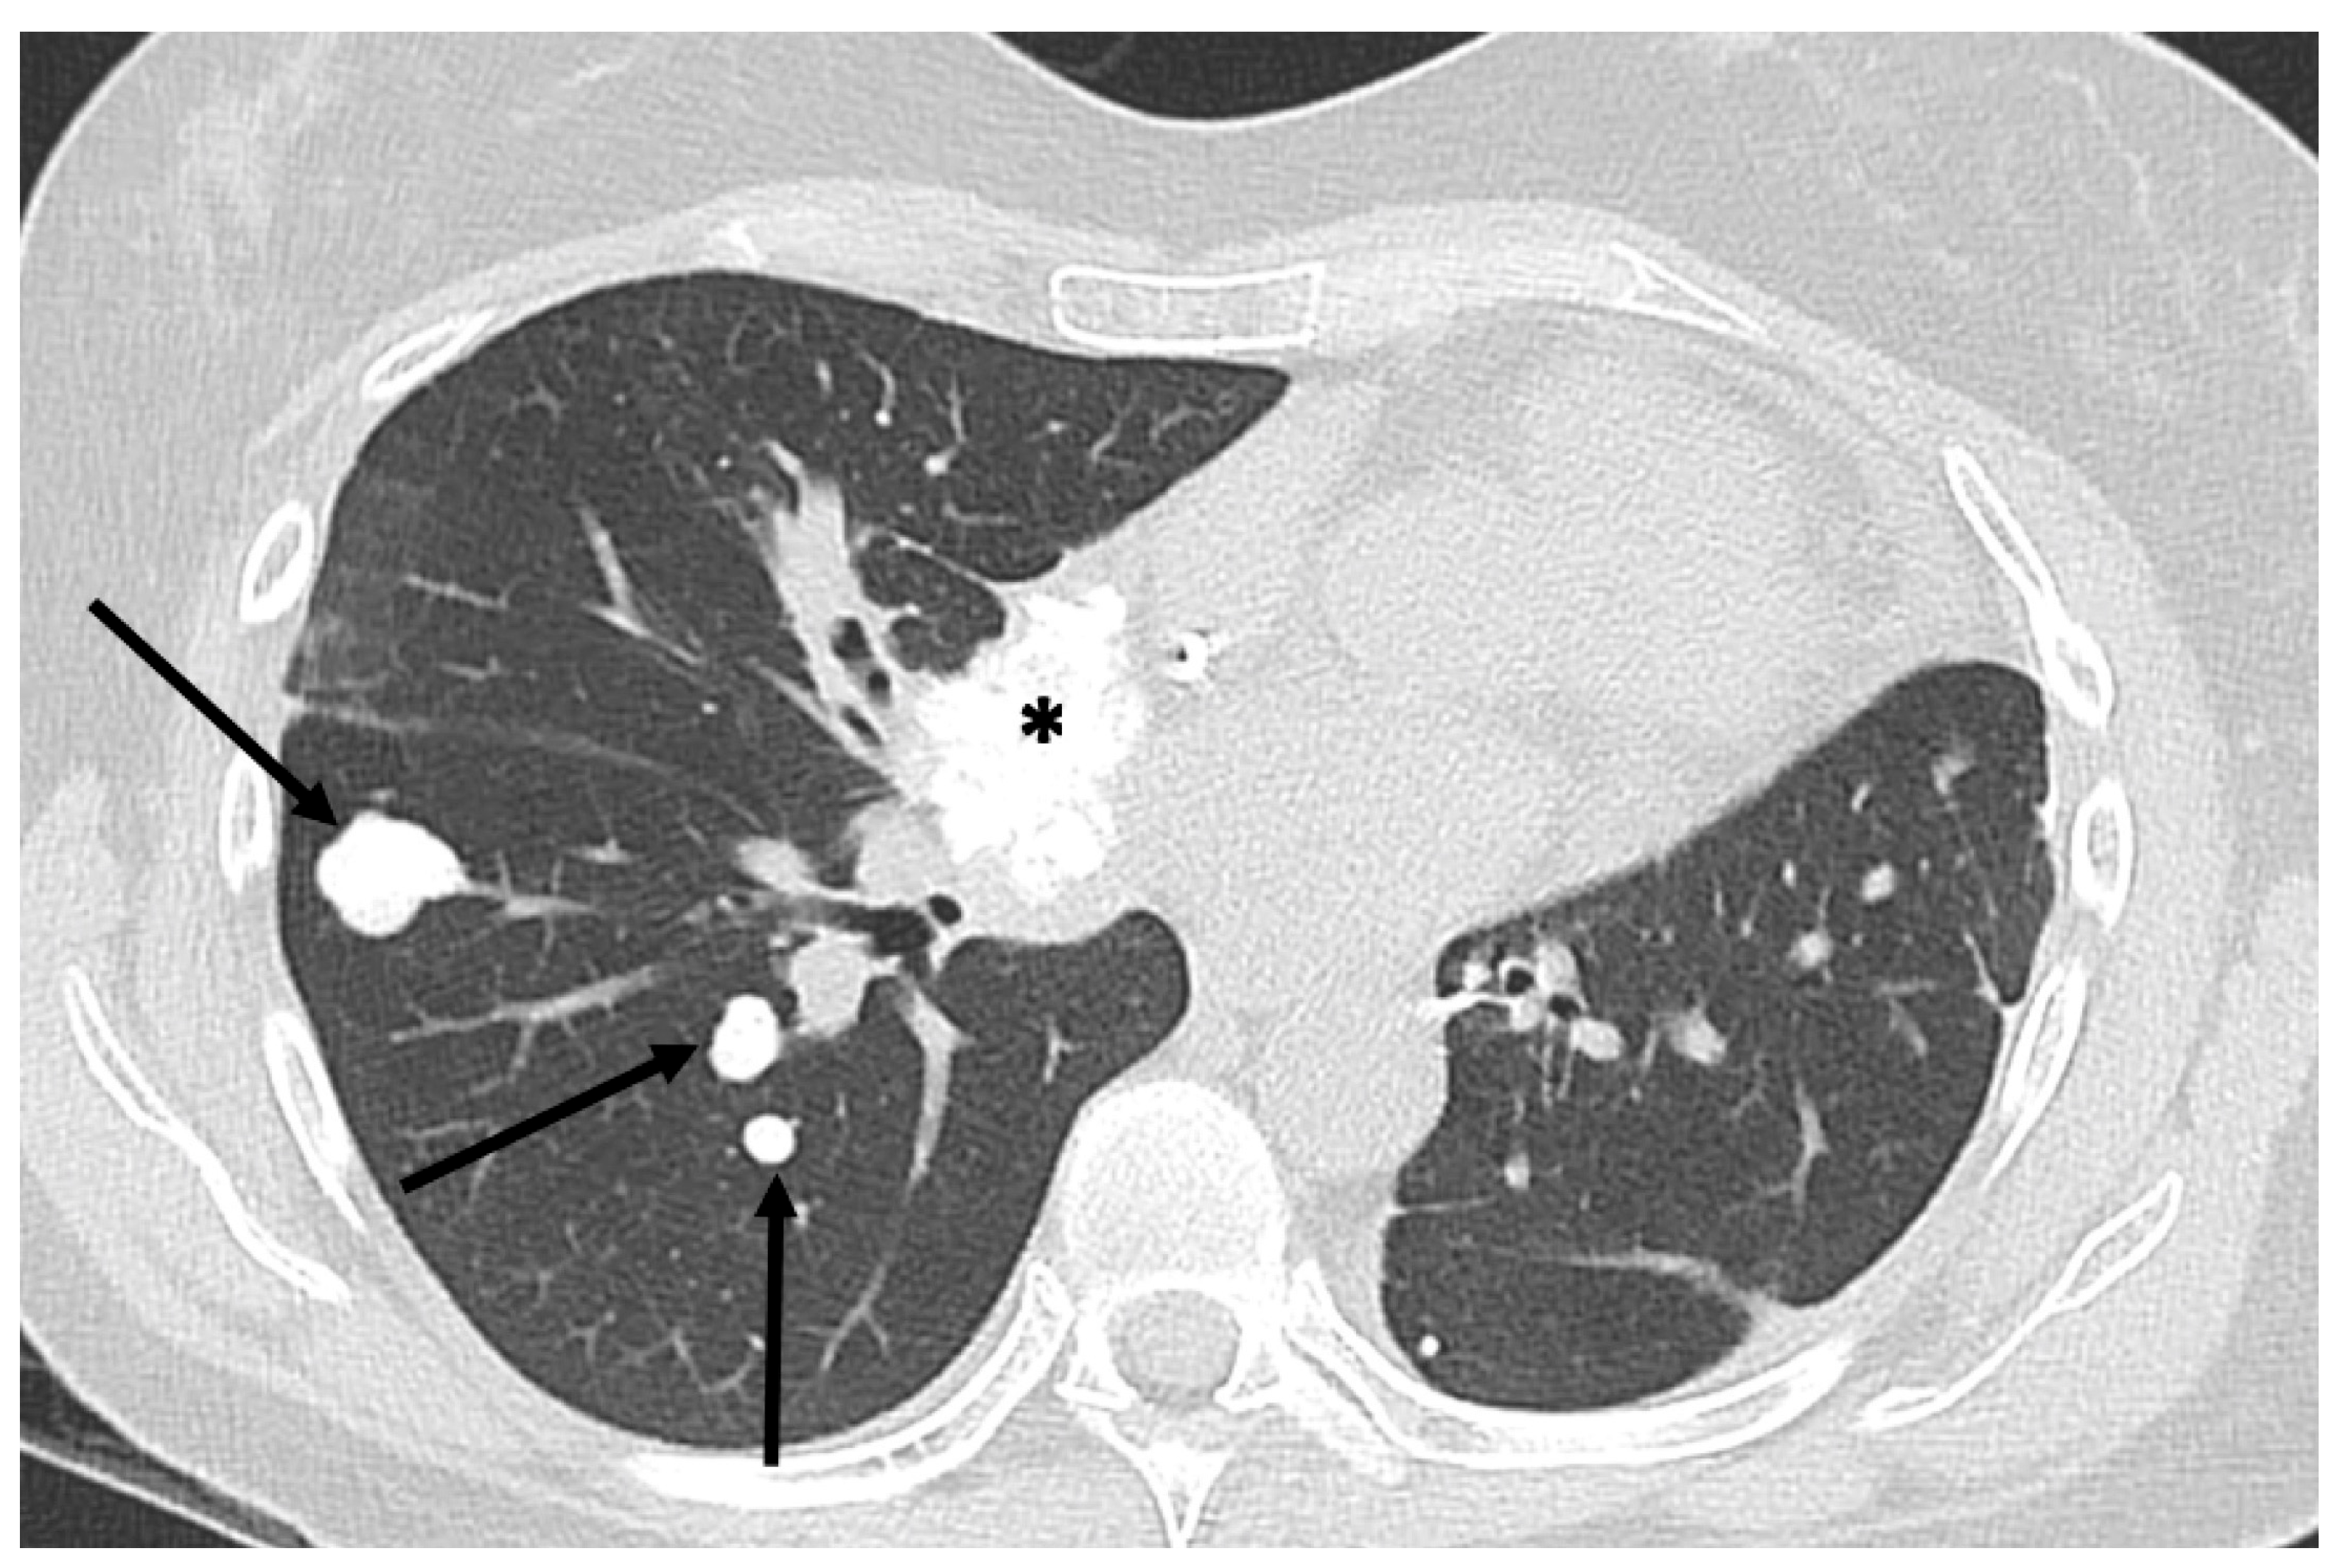

- Chiesa, A.M.; Spinnato, P.; Miceli, M.; Facchini, G. Radiologic Assessment of Osteosarcoma Lung Metastases: State of the Art and Recent Advances. Cells 2021, 10, 553. [Google Scholar] [CrossRef] [PubMed] [PubMed Central]

- Ciccarese, F.; Bazzocchi, A.; Ciminari, R.; Righi, A.; Rocca, M.; Rimondi, E.; Picci, P.; Bacchi Reggiani, M.L.; Albisinni, U.; Zompatori, M.; et al. The many faces of pulmonary metastases of osteosarcoma: Retrospective study on 283 lesions submitted to surgery. Eur. J. Radiol. 2015, 84, 2679–2685. [Google Scholar] [CrossRef] [PubMed]